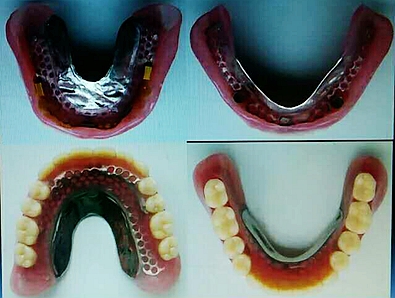

毛國斌種植病例——群討論分享